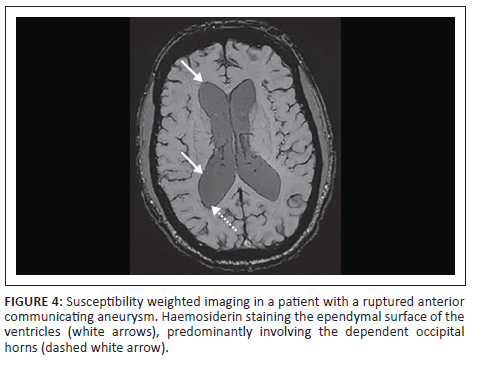

Previous T2* studies in chronic ASAH showed poor sensitivities in the detection of haemorrhage in the ventricular system. Mulé et al. demonstrated a sensitivity of 10%.16 This was thought to be related to high CSF flow velocities in these locations, preventing adequate time for haemosiderosis.12,13,16 The current study contradicted this with increased sensitivity of 62.5% for haemosiderin, even exceeding regions seen on the initial NECT as depicted in Figure 4. These areas of haemosiderin identified on SWI were located in the dependent regions of the ventricular system (occipital horns of the lateral ventricles and dependent lateral recesses of the 4th ventricle).

Two postulated reasons were thought to account for this. Firstly, the inherent increased sensitivity and high-resolution imaging of SWI compared with T2* resulted in a greater sensitivity. Secondly, over time there is reflux of haemorrhage from the cisterns into the ventricular system in patients with subarachnoid haemorrhage as shown in previous studies.8,19 This process is thought to occur to equalise CSF pressures and may show haemosiderin in the ventricular system in patients who initially did not have intraventricular haemorrhage.